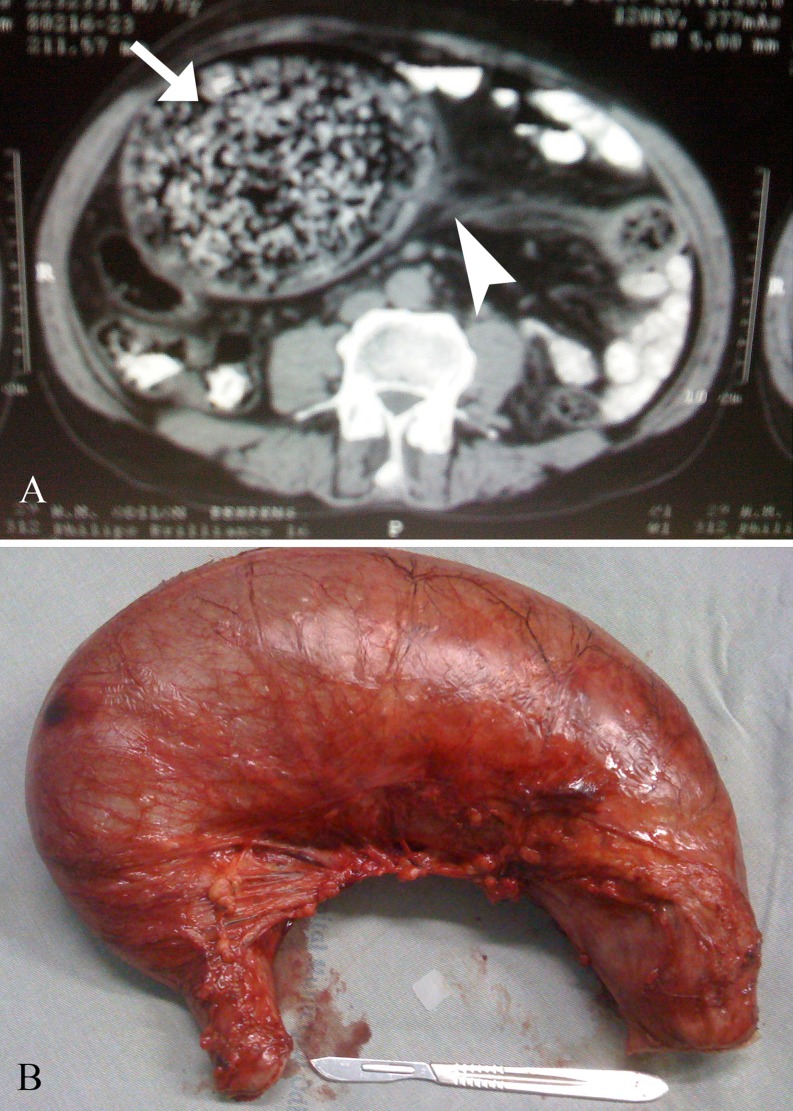

Because of doubt among fecaloma and SV, we decided to perform an abdominal CT to clarify the diagnosis. The exam revealed dilated colon filled with feces, as well, the “whirl sign” composed of mesentery and twisted colon (Fig. 1a).

a Abdominal computer tomography scan showed the “whirl sign” composed of mesentery (arrow head) and the twisted dilated colon, full with air and feces (arrow). b Surgical specimen (dilated sigmoid colon)

The patient underwent a laparotomy and sigmoidectomy with Hartmann procedure (Fig. 1b). Later he was discharge home with out any intercurrent.